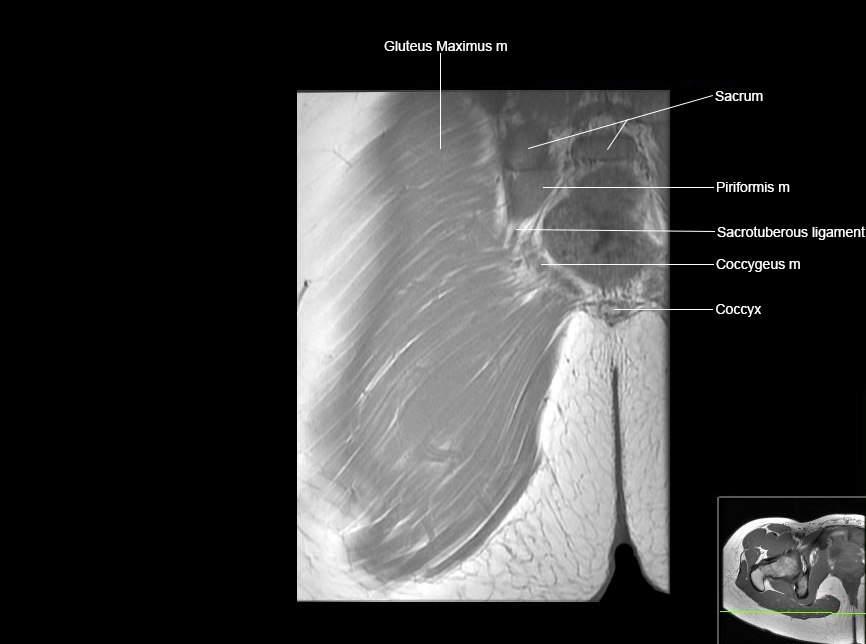

Hip

Basic Hip MRI

MRI Hip Anatomy

Scroll using the mouse wheel or the arrows